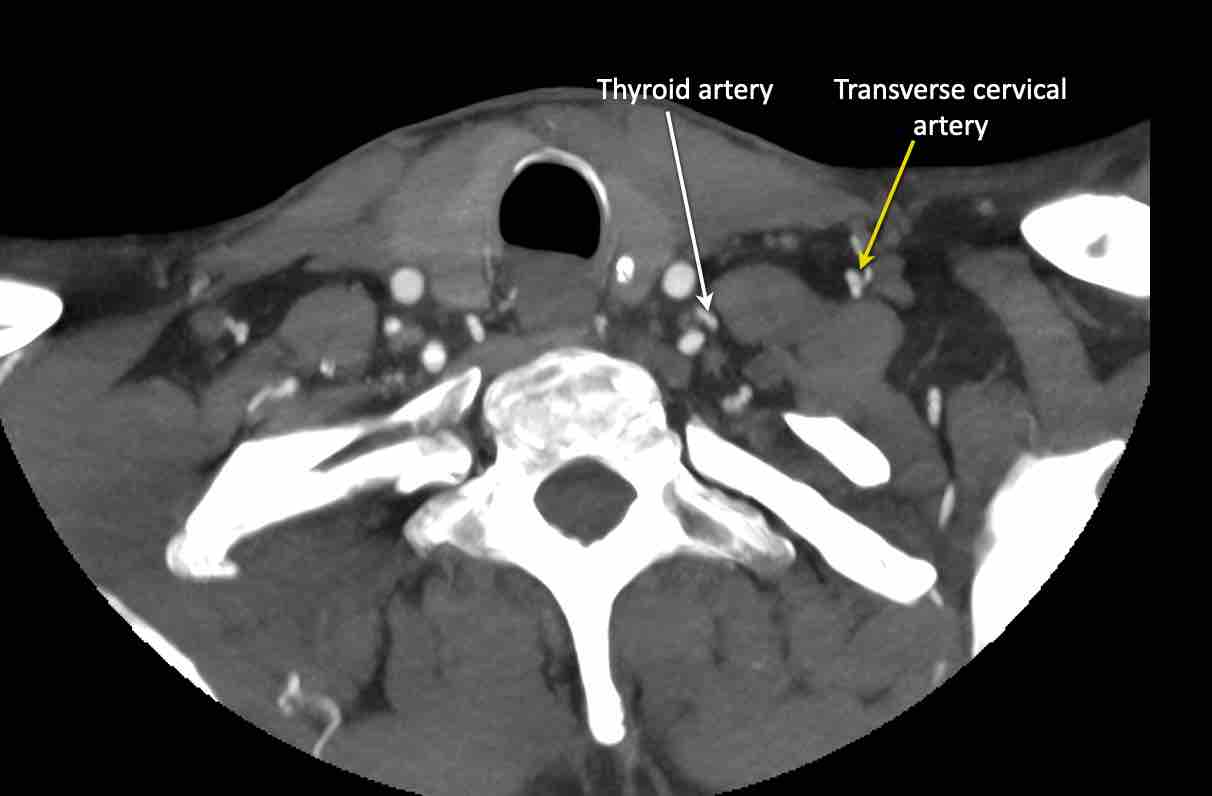

Động mạch cổ ngang

Cuộn qua các hình ảnh để xem giải phẫu của động mạch cổ ngang.